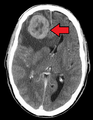

تختلف أعراض وعلامات النقائل باختلاف موقع الورم. في البداية، تُصاب الغدد الليمفاوية المجاورة في وقت مبكر. وأكثر المواقع عرضًة للانتشار من الأورام الخبيثة الصلبة[9] هي الرئتين، الكبد، الدماغ والعظام.

- الدماغ: الأعراض العصبية مثل الصداع، التشنجات، والدوار